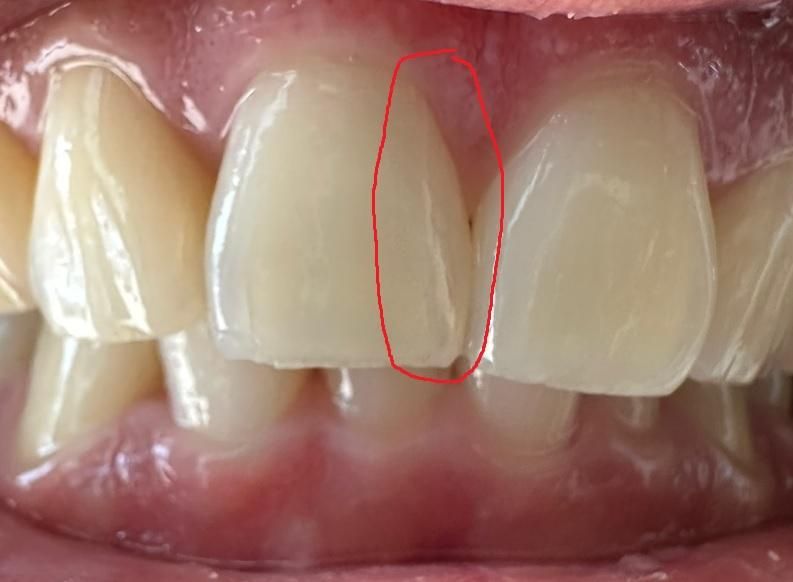

이거 치아에 선이 있는데 크랙인가요?

빨간색으로 표시한 선이 크랙인가요? 아니면 그냥 크레이지 라인(실금)인가요?

현재 이빨로 음식 씹어도 통증없고, 두들겨도 통증 없고, 찬물 먹어도 시린거 없습니다.

이빨 흔들림도 없구요.

증상이 없다면 실금입니다. 이런 경우 당장은 치료가 필요하지 않습니다. 하지만 사진을 보니 동일 치아의 끝부분도 조금 깨져나갔네요. 평소 앞니에 힘이 많이 가해지는 것 같으니 가급적 앞니로 베어물거나 뜯어야하는 음식들은 작게 잘라서 드시고, 질기거나 단단한 음식은 피해주시는게 좋을 것입니다. 금이 간 부분은 시간이 지나도 회복되지 않고 점점 진행만 되기 때문에, 힘을 잘못받으면 금이 치아안쪽까지 진행될 수 있습니다. 그렇게 되지 않도록 최대한 조심해서 사용하세요.

명확히 크랙라인이 보이긴 하나 내부까지 진행되지 않아 증상은 없는 것 같습니다. 말씀하신 craze line (실금, 치관잔금)보다는 좀 더 진행된 단계이긴 합니다.